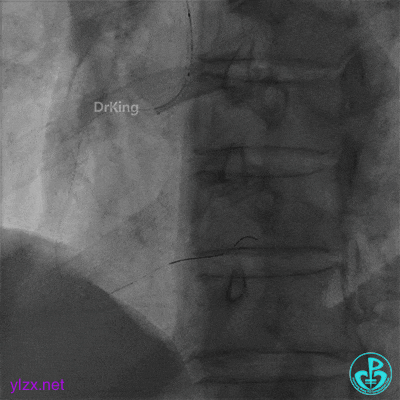

心脏叩击后恢复窦性心律,阿托品1mg静推,去甲肾上腺素静脉滴注,冠脉内推注尿激酶原20mg。

快速串联植入3.5×29mm、3.5×23mm支架。

并反复经刺破球囊冠脉内静推硝普钠5次(100μg/次),右冠脉血流恢复TIMI 3级,右冠脉近端可见夹层。